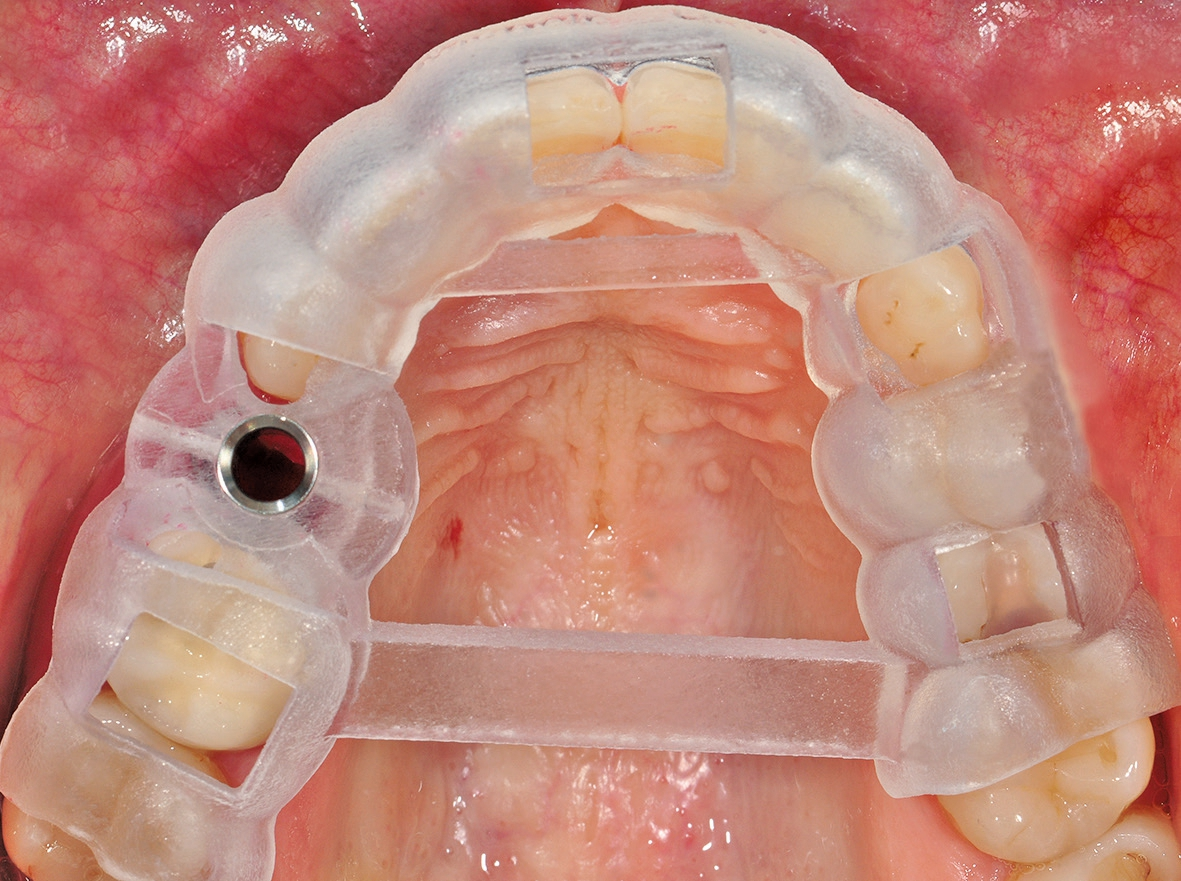

Um eine dreidimensionale Planung vornehmen zu können, wurde ein DVT erstellt und die Bilddaten wurden in die Planungssoftware 3Shape Implant Studio (3Shape, Kopenhagen, Dänemark) transferiert. Dort konnte die Implantation virtuell vorgenommen und in allen Raumdimensionen optimiert werden. Auf dieser Grundlage wurde eine Bohrschablone zur Teilnavigation hergestellt. Mittlerweile ist auch eine vollnavigierte, hülsenlose Implantation mit dem ceramic. implant möglich, das im Rahmen einer klinischen Studie eine noch präzisere Positionierung als bei den gängigen hülsengeführten Bohrschablonen zeigte [10].

Nach sorgfältiger Kürettage und Inspektion einer idealen Knochenalveole vom Typ I [11] konnte mit der Sofortimplantation begonnen werden. Die ersten beiden Pilotbohrungen wurden teilnavigiert mit der Bohrschablone durchgeführt. Das restliche Bohrprotokoll wurde nach den Vorgaben des Herstellers frei durchgeführt. Mit der Insertion des Implantats konnte die nötige Primärstabilität von 35 Ncm für eine sofortige provisorische Versorgung erreicht werden. Im Vorfeld war ein Situationsmodell der Ausgangssituation und darauf eine Tiefziehschiene vorbereitet worden, die jetzt für die intraorale Herstellung des Provisoriums mit fließfähigem Kompositmaterial verwendet wurde. Als stabilisierende Gerüststruktur diente dabei die präzise sitzende Einbringkappe (insertion.transfer) auf dem Implantatkopf, die zuvor auf die entsprechende Höhe eingekürzt worden war. Nach der Ausarbeitung und okklusalen Adjustierung der Krone wurde diese provisorisch zementiert.